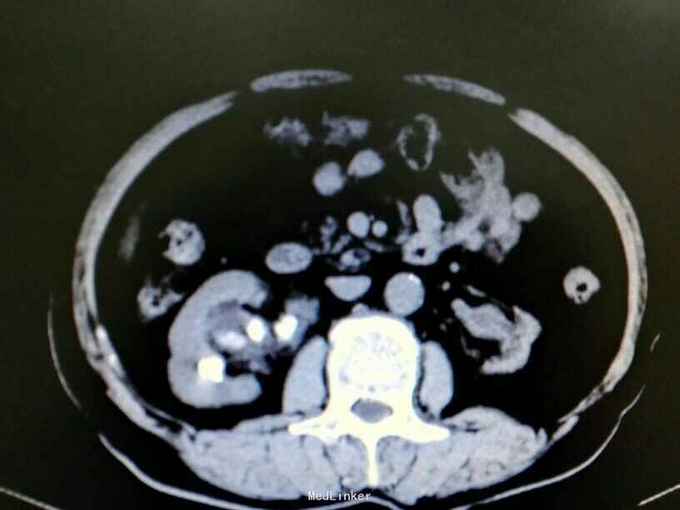

双肾铸型结石伴左肾萎缩一例

72岁男性,因“体检发现双肾结石1月”。既往10年前因双肾结石行双侧肾盂切开取石术(具体不详)。4年前因右肾输尿管结石行右侧输尿管碎石术。

双肾区叩痛。尿常规白细胞1500个/ul,两次尿培养阴性。左肾GFR15右侧38.9。

双肾铸型结石 左肾萎缩,尿路感染,双肾盂切开取石术后,BPH。经抗感染等治疗后,现在尿常规白细胞395.4个/ul。